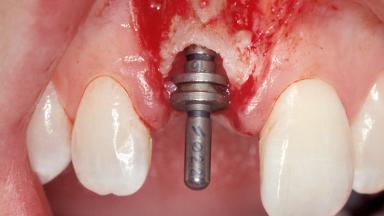

Immediate Placement of an Implant in a Maxillary Right Central Incisor Site

A 30-year-old female patient was referred to the office for the treatment of tooth 11. Her chief concern at the initial visit was to inquire, “Why is my tooth pink?” Upon clinical examination, it was determined that tooth 11 had a previous history of trauma and that the clinical crown had become noticeably pink in color as a result of internal resorption. This diagnosis was confirmed radiographically, indicating a large radiolucency involving the central and distal portions of the clinical crown. It was determined that restoration of this tooth was not possible, and that extraction was indicated. The presence of a mid-line diastema, which the patient wanted to reproduce, directed the treatment plan for tooth replacement utilizing a dental implant.

Placement Protocol Immediate implant placement

Socket Morphology Single-root socket

Socket Integrity Sufficient, with intact bone walls

Bone Volume Sufficient, with intact walls